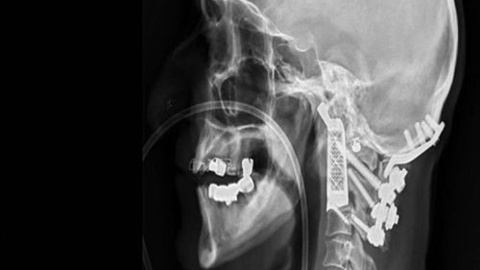

Avustralya, Sidney şehrindeki Prince of Wales hastanesinde görev alan beyin ve sinir cerrahı Ralph Mobbs, sağlık tarihine geçecek bir çalışmaya imza attı ve bir hastasının 2 omurgasını, 3D baskı teknolojisi ile hazırlanan omurga ile değiştirdi. 60 yaşlarında olan ve yakalandığı Kordoma adı verilen bir hastalığa sahip olan hastası için yapılan bu ameliyat olumlu sonuç verdi. Kordoma, omuriliğe baskı yapan ve sıkıştıran bir çeşit kanser hastalığı olarak tanımlanıyor.

Bu hastalığın en ciddi sonuçlarından biri ise el ve ayakların felç olması. Ameliyata alınan hastada değiştirilmesi planlanan 2 omurga ise hastanın kafa hareketlerine izin veren omurgalardı.  Bu iş ise düşünüldüğü kadar kolay olmayan ve 3D teknolojisinin işin içine dahil edildiği nokta oldu.

Mobbs, Avustralya merkezli medikal cihaz üreticisi Anatomics ile bir çalışma yaptı ve titanyumdan hazırlanan birebir uyumlu 2 omurga hazırladılar. Bu gelişme ise tarihe bir ilk olarak geçti. Hazırlıkların ardından 15 saatlik ameliyat süreci başladı. Operasyon bölgesi ise beyin kökü, bazı ana damarlar ve omurilik bölgesinin hemen üstünde, yani son derece riskli ve dikkat edilmesi gereken bir bölgedeydi.  Ameliyatın en zor kısımlarından bir ise hastanın başını boyundan ayırıp, tümörlü bölgeyi temizleyip, başı tekrar boyuna yerleştirmekti. Mobbs ve ekibinin 15 saatlik operasyonu ise başarıyla sonuçlandı.